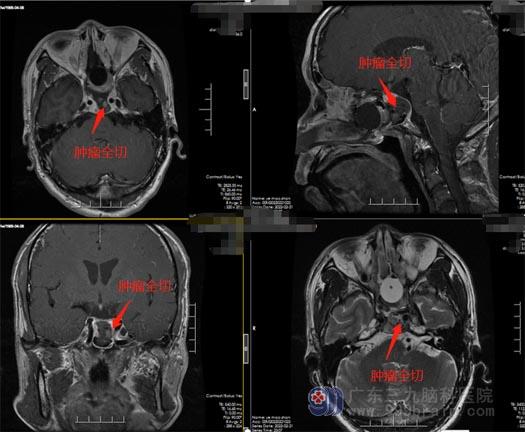

叶先生十分担心开颅手术会影响到他的工作,王国良主任告知不开颅就可以把肿瘤切除了。手术由鲁明副院长、王国良主任带领外五科神经内镜组团队进行,在内镜下经鼻蝶垂体瘤切除术,术中肿瘤全部切除,周围神经及组织血管保护完好,视神经压力解除,术后叶叔视力明显好转,没有出现手术后尿崩、离子紊乱、视神经损伤等术后并发症。

神经内镜经鼻垂体瘤切除术是一种常见的神经外科微创手术,手术时间短、出血少、并且术后恢复的时间也很短、大多数可以得到非常良好的恢复。